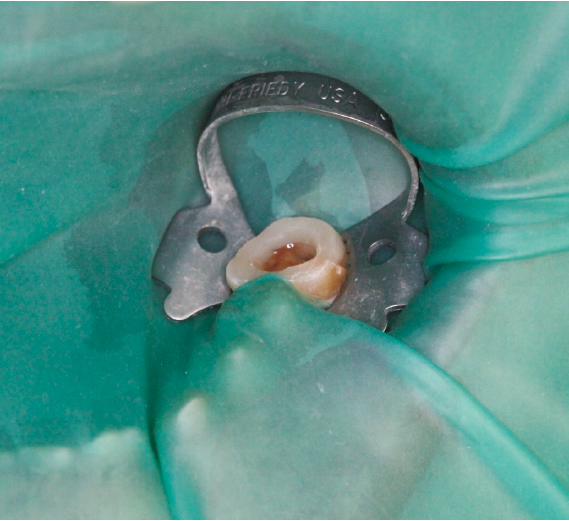

当院に来院される患者さんの多くは『他院で抜くしかないと言われる歯をなんとか残して欲しい』と言う希望の元来られます。現在歯を失う大きな原因となっている3大原因は『虫歯、歯周病、破折』です。多くは虫歯や破折なのですがこう言った歯の場合の治療には根管治療が必要になることがほとんどです。根管治療とは簡単に言うと、『ラバーダム』(写真1)と言われるゴムのカバーを歯に取り付け、根っこの中にある汚れを隅々まで取り、できる限り無菌に近い状態にして最後に蓋をする、と言う一連の流れになります。そしてその際に根っこの中にヒビが見つかったり根っこの中からのお掃除では綺麗になりきらず治癒しない場合は再植と言う治療になります。再植は『一回歯を抜いてお口の外でその歯を治療し再びお口の中に戻す』と言うものです。(写真2)『抜いた歯を再び植える』と言うことで再植と言う名がついています、他の方法で違う場所から歯を持ってきて(移動してきて)植える事を『移植』と呼んだりしてます。こちらの移植の方が臓器等、医科の分野でも使われる技術なので皆様には馴染みがあるかもしれませんね。